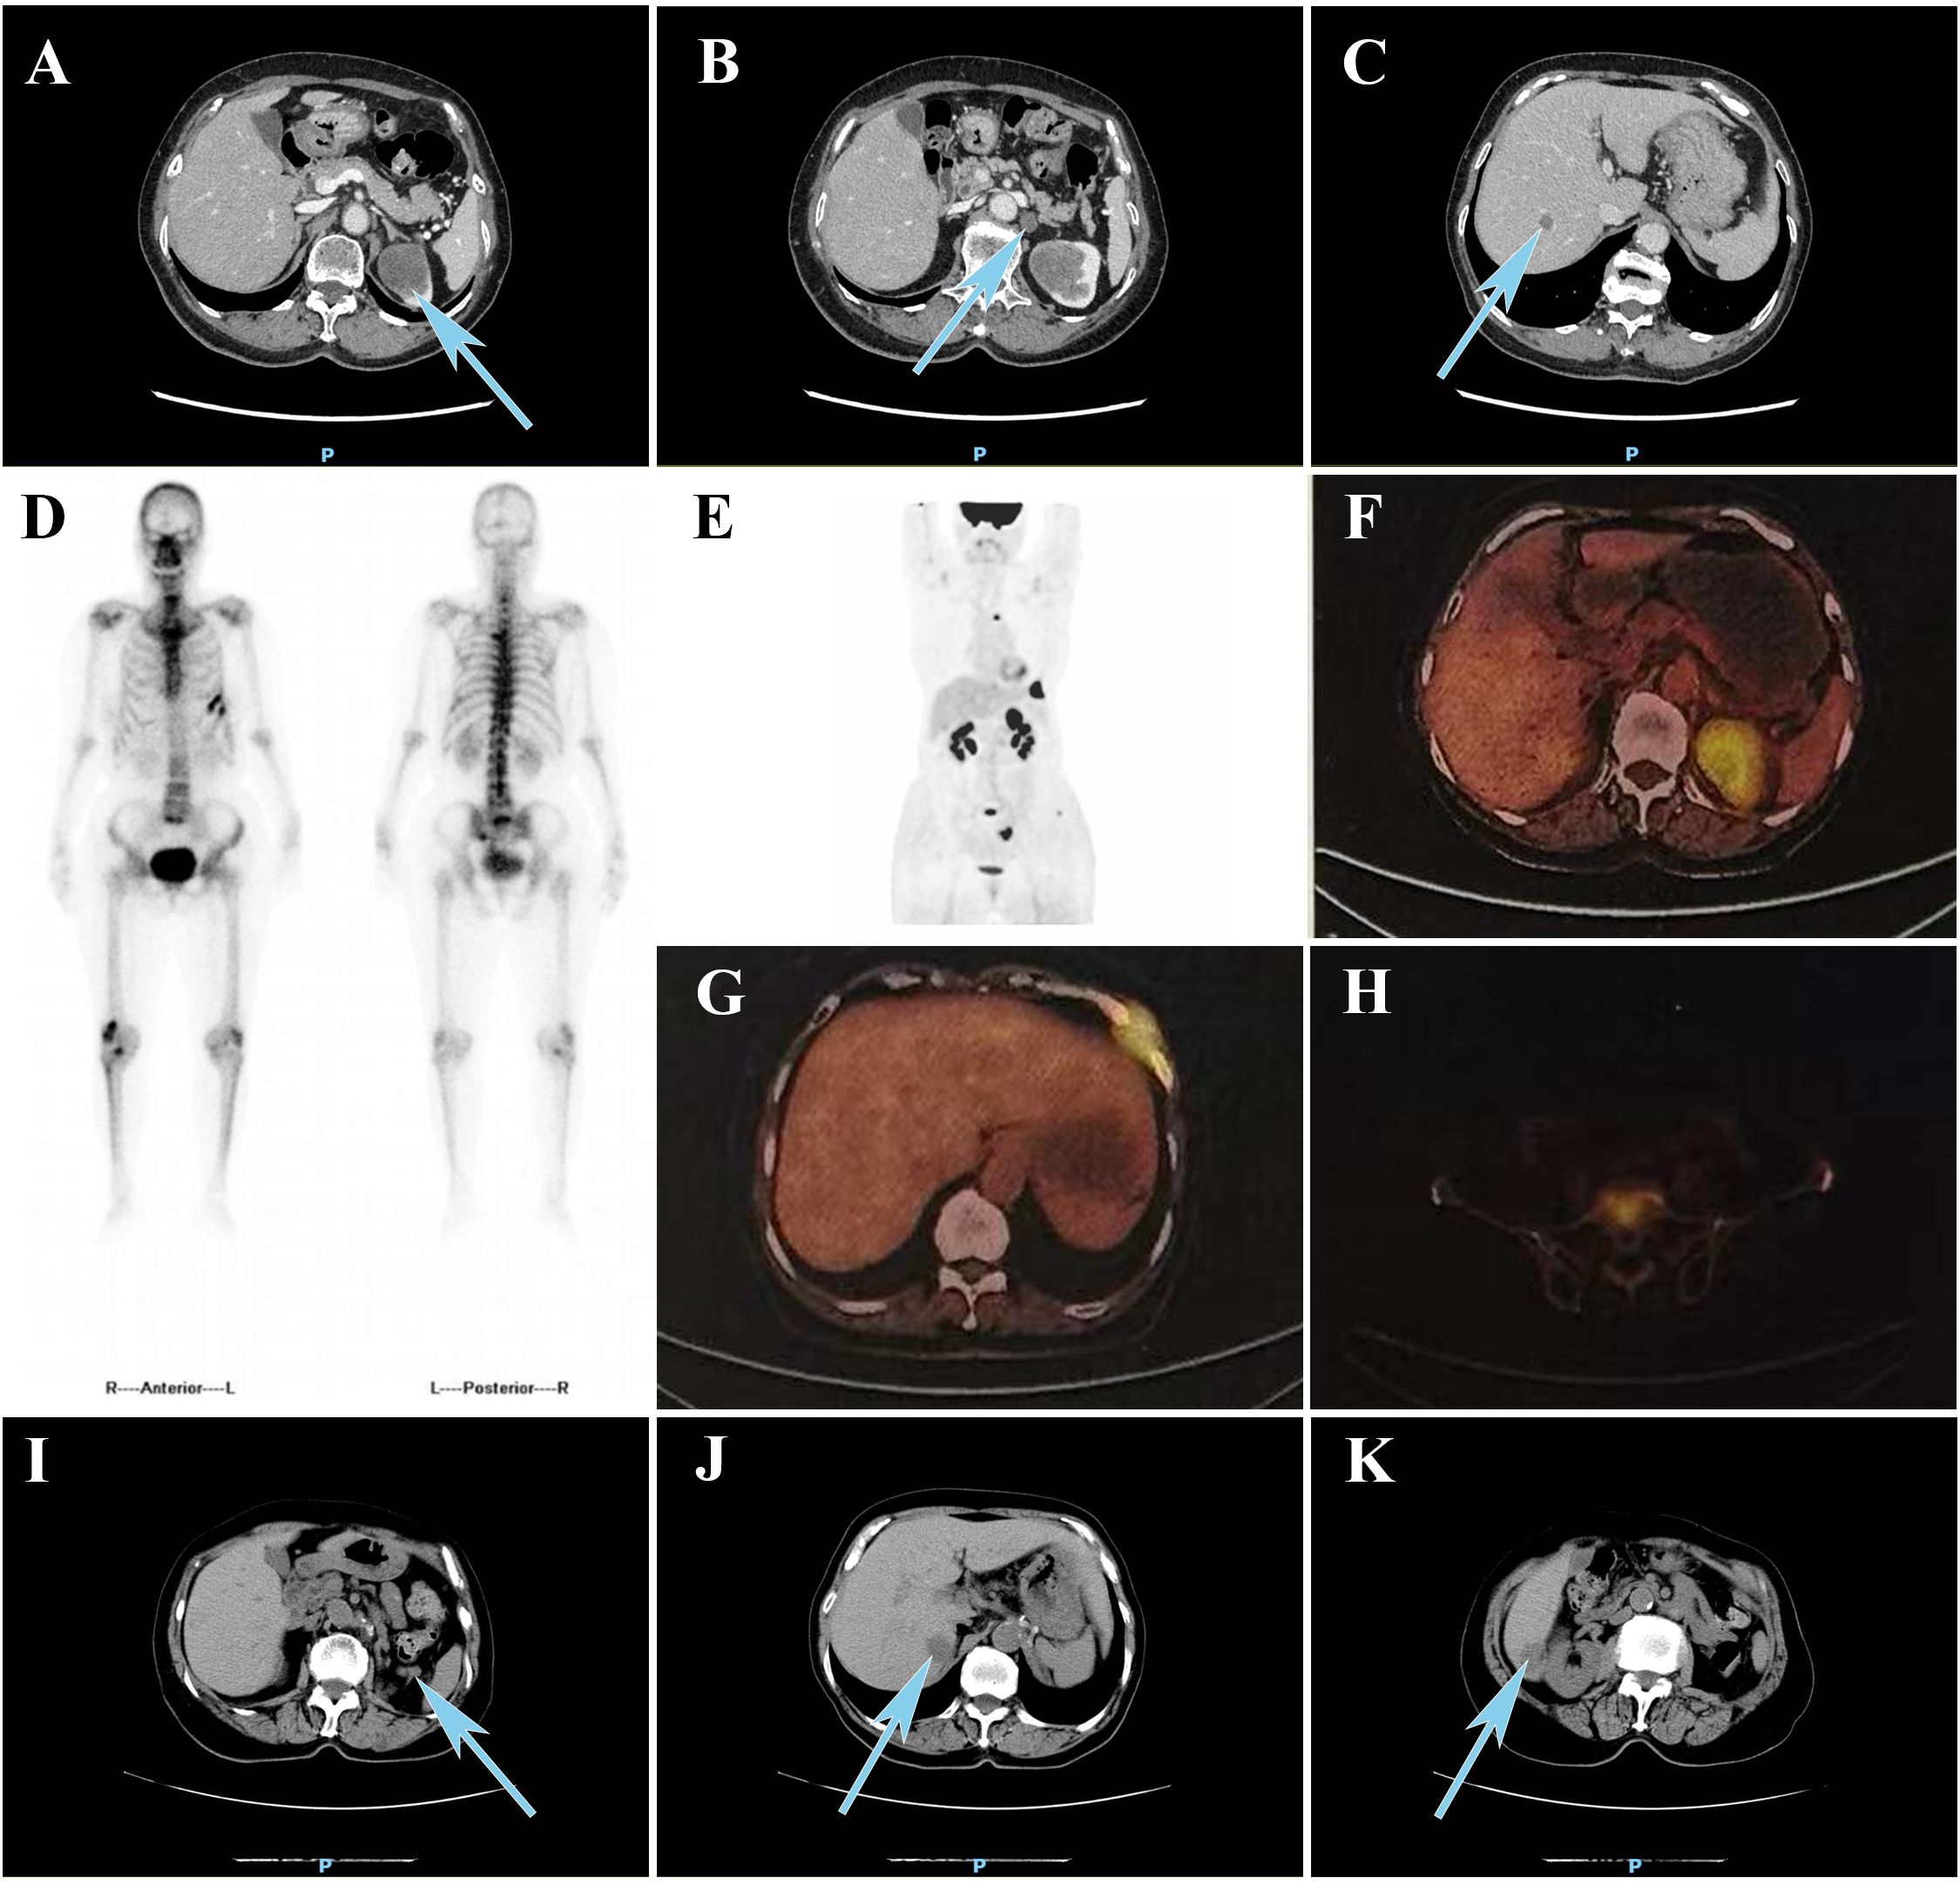

SMARCA4-deficient tumors represent a highly aggressive subtype of malignancy defined by the loss of SMARCA4 expression, and are associated with rapid progression and poor prognosis. We report the first documented case of SMARCA4-deficient renal cell carcinoma (RCC) in an adult (pT3aN1M1, Stage IV), characterized by sarcomatoid and rhabdomyoblastic differentiation, aggressive clinical behavior, and resistance to standard systemic therapies. This case provides a comprehensive analysis of clinical, pathological, imaging, and genetic findings, offering insights to refine diagnostic, therapeutic, and preventive strategies for this rare malignancy.